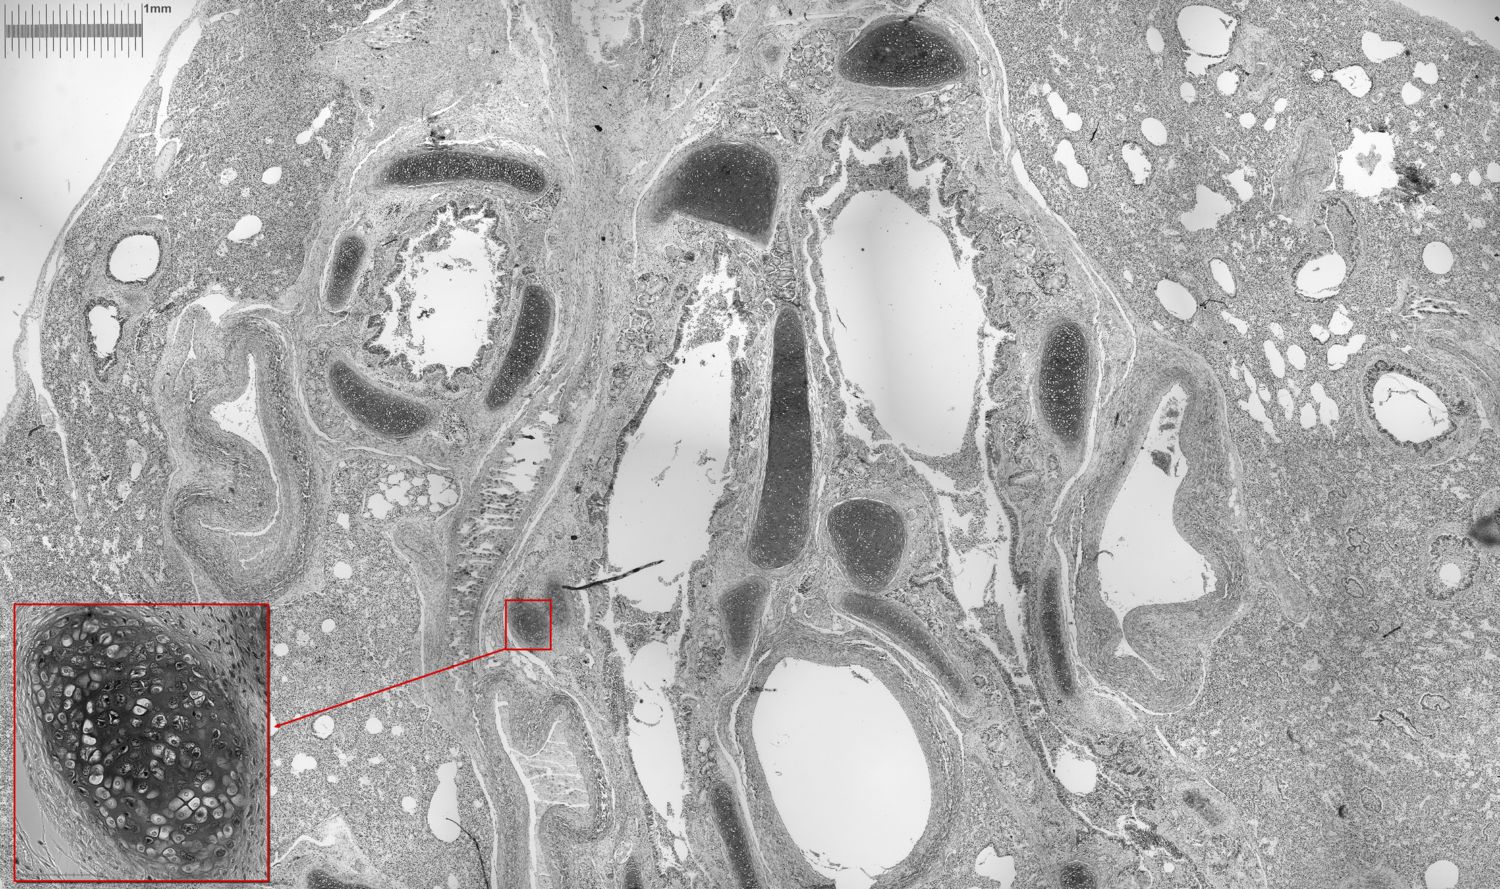

Une lame récupérée dans un labo de biologie, c'est une coupe de tissu humain : objectif Letz Leica Plan 4x, Sony A7S

image.thumb.png.f296355e76ecdd377a38c757692a0e70.png

On zoome dans l'image avec Leitz Plan 20x :

image.thumb.png.39996eb2123a768ff50adb93c36d5d2a.png

On zoome encore avec le Nikon Plan APO 40x/0.95 : on commence à bien voir les cellules humaines et leur noyau !

image.thumb.png.ded570a1f6a1ccfebc4b7f1200eb35e1.png

Et enfin la même avec une caméra astro N& avec l'échelle à côté :)

Un noyau de cellule mesure 5µ de diamètre !

image.thumb.png.c4fed413520e668e9dbca636ecce2b1d.png